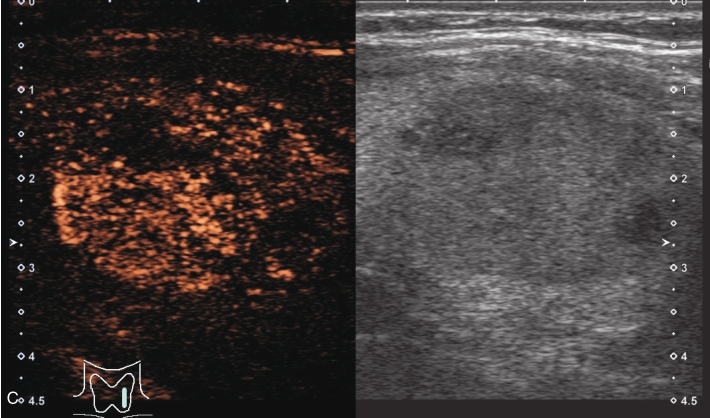

甲状腺左叶中下部见一混合回声结节,边界清,形态规则,中心部可见斑状强回声,CDFI显示周边可见环状血流信号,其内可见丰富血流信号,见图1-3-18。

该结节早于周围腺体组织增强,结节内部呈高增强表现,可见部分无增强区;结节晚于周围腺体组织消退,仍呈高增强表现;结节周边可见均匀高增强环,甲状腺被膜未见明显中断,见图1-3-19、ER1-3-9。

(1)结节增强早期早于腺体增强或与腺体同步增强,增强晚期晚于腺体消退或与腺体同步消退。

(2)结节内部呈均匀或不均匀弥漫性等增强或高增强,增强水平通常高于周围腺体。

(3)结节与周围腺体分界清晰,形态较规则。

(4)部分结节周边可见均匀高增强环。

(5)结节周边被膜连续完整。

甲状腺滤泡性腺瘤通常为富血供病灶,其增强水平等于或高于周围腺体,并呈现“早增强,晚消退”的特点,重点需要与滤泡性腺癌鉴别,腺瘤多边界清晰、形态较规则,造影时结节周围的高增强环厚薄一致、较为均匀,结节周边被膜连续完整、无浸润表现,颈部淋巴结无异常肿大等。而滤泡性腺癌边界不清、呈浸润性生长表现,周边高增强环消失或厚薄不均,如发现颈部异常肿大淋巴结及被膜连续性中断等,需要高度警惕甲状腺恶性肿瘤。

图1-3-18 甲状腺滤泡性腺瘤常规超声声像图

A.甲状腺左叶纵切面超声图像;B.结节内部点状及斑状强回声;C.CDFI血流图